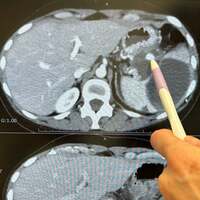

ミミポポはブログの冒頭で、「急遽明日から入院します」と切り出し、年内最後の抗がん剤治療を行うはずだったが、血液検査の結果、アミラーゼの値が跳ね上がったことから、急遽造影CTを撮ることになったと告白した。「そしたら...膵臓はなんともなかってんけどまさかの、、また!動脈瘤が出来てたのを発見して…!!」と述べ、6月ごろに撮ったCTと比較しながら医師が指摘した箇所が動脈瘤であることを説明。

それに対し、破裂する前に見つけられたことが幸いとし、年末にもかかわらず、入院と手術が年内に行えることになったと安堵の気持ちを表した。「26日に入院、27日に手術、29日に退院の予定」と詳細なスケジュールも明かしつつ、「自分責めても仕方がないし 誰のせいでもない 天に身を任せてやれることをやっていこう」「自分を責めるより未来に期待して今を精一杯やっていこう!今はそんな風に思ってるん」と前向きな姿勢を示した。